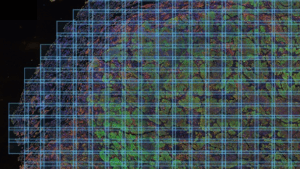

What it is: AstroPath consists of high-fidelity, whole-slide spatial maps of the tumor microenvironment (TME), profiling 100,000–2 million cells per slide to offer an unprecedented single-cell view of tumors. SciServer hosts the public release of the AstroPath datasets. Additional information on AstroPath can be found on our science domain page.

The letters in each AstroPath dataset’s project ID indicate the experimental protocol or platform used (e.g., apmifwsi stands for AstroPath Multiplex Immunoflourescence Whole-Slide Imaging), while the numbers correspond to a specific collection of specimens — typically derived from a single scientific study and processed under consistent experimental conditions. Each dataset is further organized into data release folders (DR##), which contain separate subdirectories for each specimen labeled using AstroID nomenclature.1

Each dataset includes a README.md file detailing the dataset contents and changes between releases. For spatial datasets, a wsi.zarr (multiscale whole-slide image in OME zarr format) and a cells.parquet file (single-cell data in parquet format) can be found within the slide folder for a given patient specimen.

The dataset is composed of multiplex immunofluorescence imaging of pre-treatment biopsies and on-treatment surgical resections collected from patients with non–small cell lung cancer who received neoadjuvant immunotherapy as a part of a clinical trial.2 Slides were stained with a 7-color panel (DAPI, PD-L1, CD8, FoxP3, Cytokeratin, PD-1, CD163), scanned on the Vectra Imaging System (Akoya Biosciences), and processed by the AstroPath pipeline to generate whole-side images and extract cell-by-cell data.